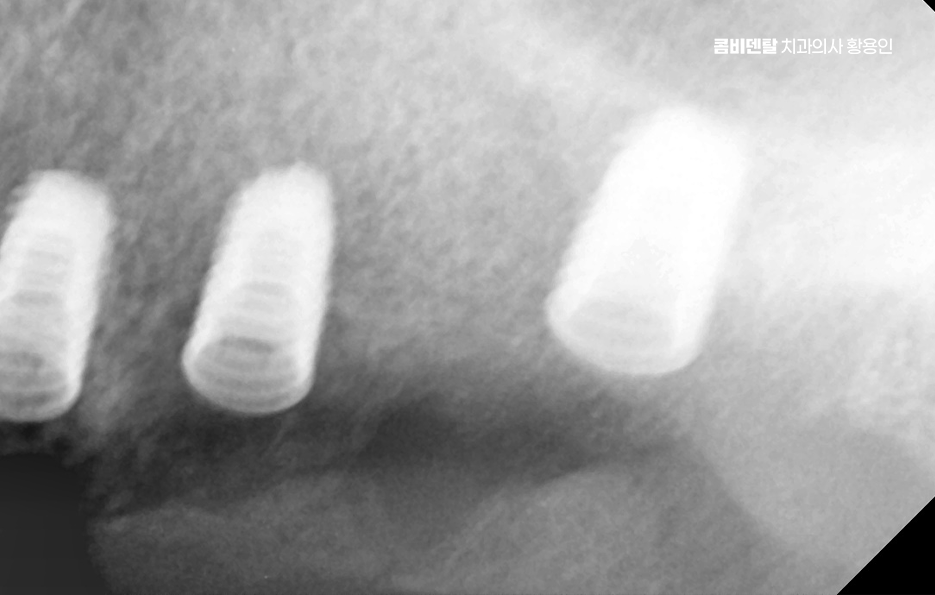

군데군데 빠진 치아를 전부 임플란트로 하나씩 심을 수도 있지만, 꼭 그럴 필요는 없으며 예를 들어 어금니 3개가 빠졌다면 3개를 다 심지 않고, 2개만 심고 그 사이를 브릿지로 연결하는 방식도 가능한데 이러한 치료 계획은 단순히 효율성이나 경제적인 측면만 따지는 것이 아니라 각 개인의 잇몸 뼈 상태와 식립 위치, 각도 그리고 사후관리까지 종합적으로 판단해야 하기 때문에 경험 많은 치과의사와 함께 충분한 상의 후에 결정해야 하는 거예요

50대임플란트 치료가 끝났다고 해서 끝이 아니라 이 시점부터 유지 관리가 무척이나 중요하며 임플란트 수명을 좌우할 수 있는데 임플란트는 영구적인 치료가 아니고 얼마나 잘 관리하느냐에 따라 수명이 달라지는 구조이기 때문에 정기적인 검진과 스케일링을 잘 실천해야 하고 집에서는 부드러운 칫솔, 치간칫솔, 치실, 필요하면 워터픽까지 활용해서 잇몸 사이 관리에 신경 써야 하겠고 음식도 처음엔 너무 질기거나 딱딱한 건 피하고, 골고루 양쪽으로 씹는 습관을 들여야 하는 등의 관리가 곧 임플란트를 얼마나 오래 쓸 수 있느냐를 좌우할 수 있기 때문에 치과 역시도 오래 함께할 곳을 잘 따져보실 필요가 있었어요